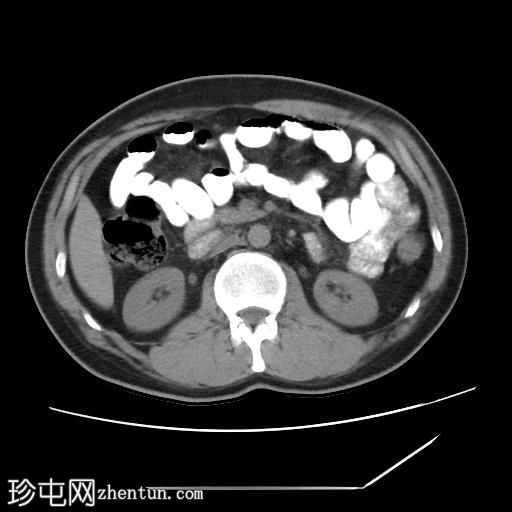

轴位增强扫描

CT扫描显示胰腺组织完全包绕十二指肠第二段。未发现胰周结节或肿块。